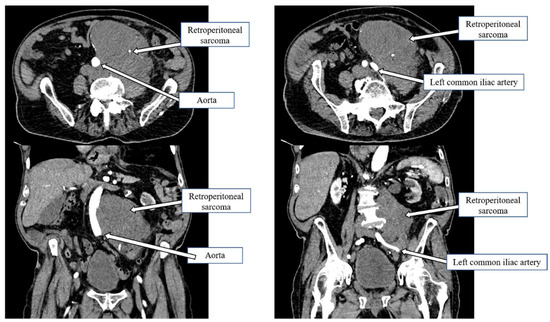

2.2. Impact of Vascular Resections on Post-Operative Outcomes